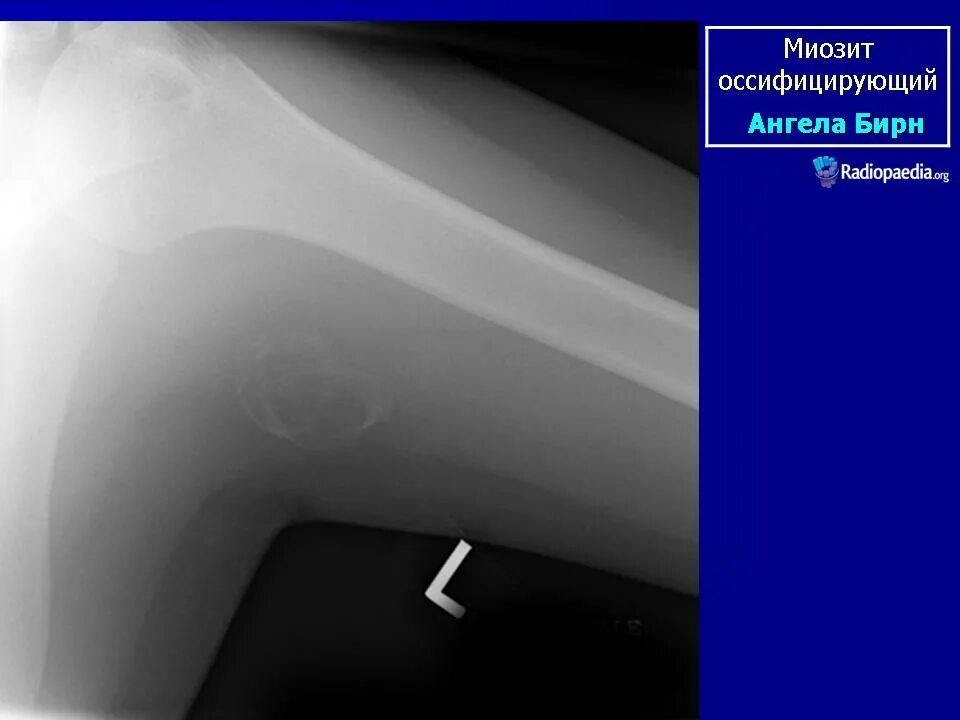

Мкб миозит мышц